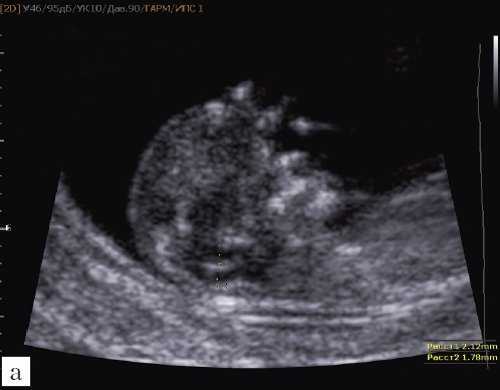

Особенностями визуализации этих структур является их гипо/анэхогенность. Так, при сроках 11-14 недель беременности таламус, ствол мозга, средний мозг выглядят практически анэхогенными. Итак, нормальная ультразвуковая анатомия этих структур головного мозга плода имеет следующие особенности: ствол и IV желудочек выглядят как анэхогенные продолговатые структуры, имеющие непосредственную близость (как бы выходящие) из диэнцефалона и среднего мозга. Все выше перечисленные анатомические структуры могут быть измерены и должно быть оценено их взаиморасположение (рис. 2, а).

а) На эхограмме:

1 - ствол мозга;

2 - интракраниальное пространство, или IV желудочек;

3 - большая цистерна головного мозга;

4 - воротниковое пространство.

Новый ультразвуковой маркер в изучении нормальной ультразвуковой анатомии головного мозга плода в срок 11-14 недель беременности

Особенности визуализации изложенных выше структур в данном сроке позволили нам выделить и назвать новый ультразвуковой маркер нормальной ультразвуковой анатомии мозга плода. Структуры головного мозга плода в этой области схожи с осьминогом, у которого есть голова и две приблизительно равновеликие по диаметру ножки, представляющие собой ствол мозга и IV желудочек. Ниже ножек "осьминожки" визуализируется 2 "подушки осьминожки" - это два анэхогенных пространства - большая цистерна и воротниковое пространство (рис. 2, б).

Так как речь идет о сроках первого скрининга, т.е. раннего осмотра, новый ультразвуковой маркер мы назвали "осьминожкой" (рис. 3).

а) Стрелками указана голова "осьминожки" - диэнцефалон (таламус).

б) Красный цвет - диэнцефалон (таламус), со стволом мозга (верхняя ножка) и IV желудочком (нижняя ножка); желтый цвет - большая цистерна головного мозга; синий цвет - воротниковое пространство.

Как сказано выше, имеет значение и измерение ножек "осьминожки", так среднее значение диаметра нижней ножки, т.е. IV желудочка в зависимости от КТР в срок 11-14 недель варьирует от 1,5 до 2,5 мм (рис. 4).